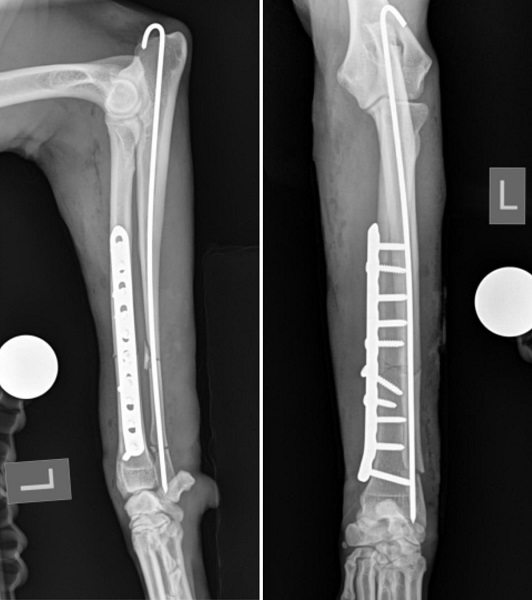

Accidents do happen… and bones do break! Bone fracture repair in dogs and cats is a skill that greatly enhances the health of our pets when the unexpected trauma of a fractured bone occurs. There are various methods of repairing fractures from simple confinement and rest with no intervention to internal mechanical fixation with bone grafts. One common method, displayed on this page, is the use of stainless steel bone plating devices to hold the fracture segments together while the slow healing process takes place.

Bone plating in dogs and cats has the distinct advantage of being secure, stable, strong and requires no external splinting or fixation hardware that would encumber normal mobility and comfort. The patient that underwent internal fixation surgery (an example of external fixation would be a simple splint or cast) in this presentation walked comfortably out the door the day after surgery and had almost no swelling or discomfort. X-rays of the healed bone six weeks later (below, right) reveal good union and new bone formation.